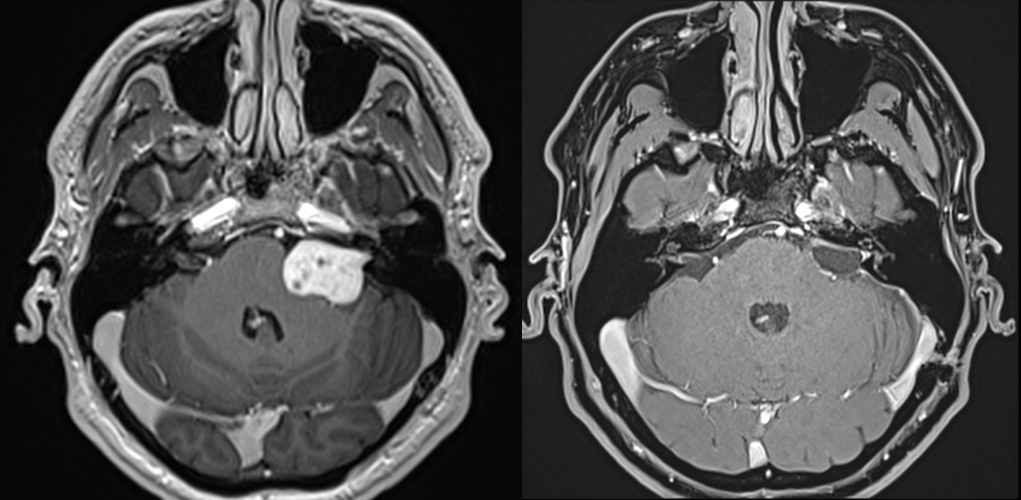

RMN cerebral cu substanță de contrast – Este cea mai precisă metodă pentru diagnostic. RMN-ul evidențiază tumora și arată dimensiunea și localizarea exactă precum și eventualele complicații (hidrocefalie). Pentru tumorile de mici dimensiuni există o secvență specială care vizualizează mai bine nervii cranieni (în funcție de tipul de aparat se poate numi CISS, TRUFI sau FIESTA).

Pe RMN, schwanomul vestibular apare ca o masă nodulară cu priză de contrast, bine delimitată, localizată în spațiul dintre stânca temporală și cerebel, cu origine în porul acustic intern.

Diagnosticul diferențial se face cu alte tumori care se pot dezvolta în această locație, în special meningioamele. Mai rar poate fi vorba și de un chist epidermoid, o determinare secundară sau o tumoră de glomus jugular. O situație aparte, deși rară, o constituie scwanoamele dezvoltate dina lți nervi cranieni – cel mai adesea nervul trigemen.